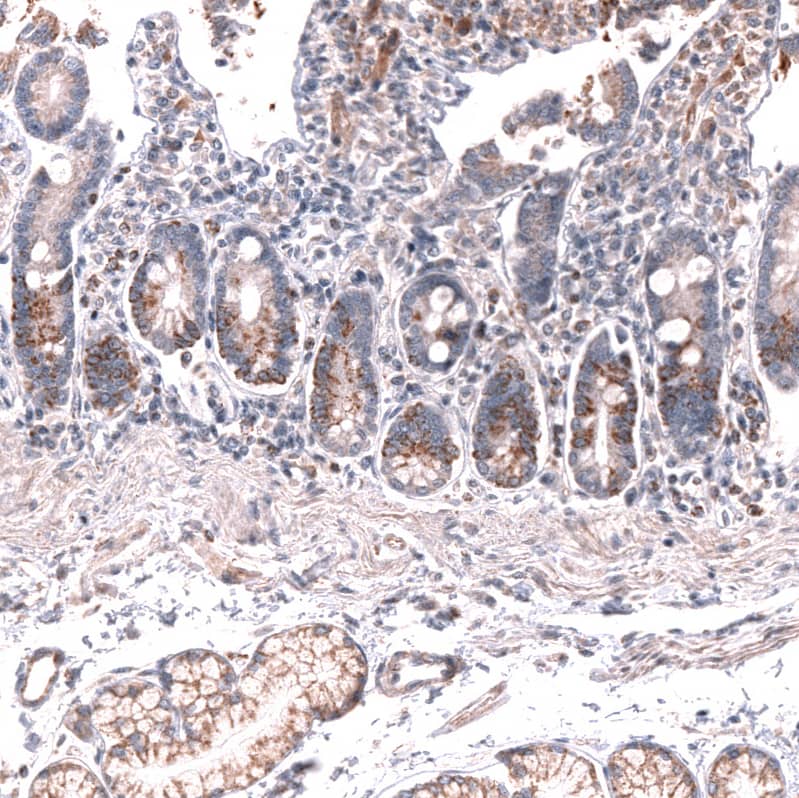

Staining of human duodenum shows moderate cytoplasmic and membranous positivity in glandular cells.